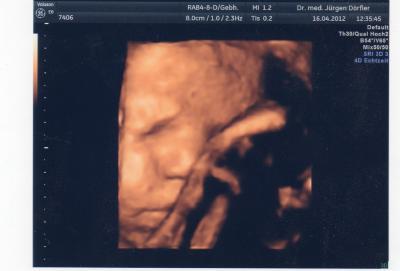

Heute morgen hatte ich VU mit CTG! Es ist alles prima! Keine Wehen auf dem CTG, der Muttermund ist noch zu,aber schon alles weich,Blutdruck war auch io.Hab auch nachmal ein Bild machen lassen,leider hat das Mäuschen immer die hand davor.grrrr... LG

Bild zu Zurück vom FA - Forum für Mai - Mamis

wie schön das bild bei mir geht das nicht mehr man kommt nicht mehr ans gesicht halte es in ehren in dem stadium noch son bild abustauben ist der knaller...

ich freue mich, dass bei euch alles tutti ist. weiter so und dann wird deine maus auch dein bauch verlassen. bissl geduld müssen wir jetzt mal aufbringen. süßes bild hast du da noch bekommen